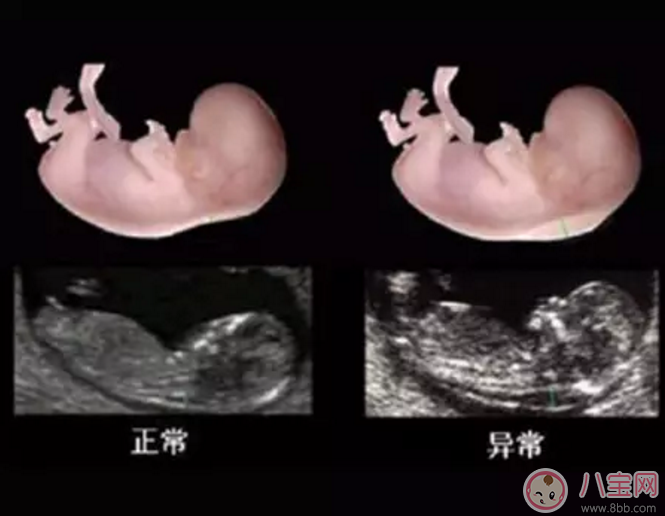

早唐篩查一般在懷孕11-13周進行,需結合血清化驗的結果和NT值來做判斷。NT值指的就是胎兒頸部透明帶的厚度(如下圖所示),可以通過B超來進行檢查。NT檢查對醫生的技術和B超的設備都有一定的要求,所以不一定每個醫院都能做。而且做NT檢查一般需要預約,需要做檢查的準媽媽要注意提前和醫生約好時間。